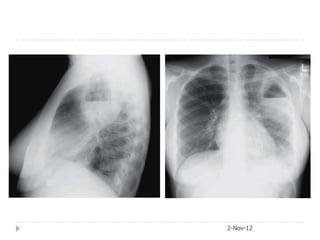

Case 5  65-year-old female presented with acute respiratory failure. She had been sick for two weeks with fever, confusion, diarrhea, cough, and purulent sputum production. Her medical checkup two months ago was unremarkable.  Urea 11 mmol/L, Creatinine 3.2  CXR and later CT chest obtained 2-Nov-12

After3 weeks courseof macrolide 2-Nov-12

• #33 A, Legionellosis, initial chest radiograph showing left lower lobe consolidation.B, Legionellosis, initial chest computed tomography demonstrates left lower lobe alveolar infiltrate and pleural effusion.

• #34 B, Legionellosis, initial chest computed tomography demonstrates left lower lobe alveolar infiltrate and pleural effusion. C, Legionellosis, chest computed tomography performed 6 weeks later (and after a 3-week course of macrolide) demonstrates partial resolution of left lower lobe alveolar infiltrate and disappearance of parapneumonicpleural effusion.